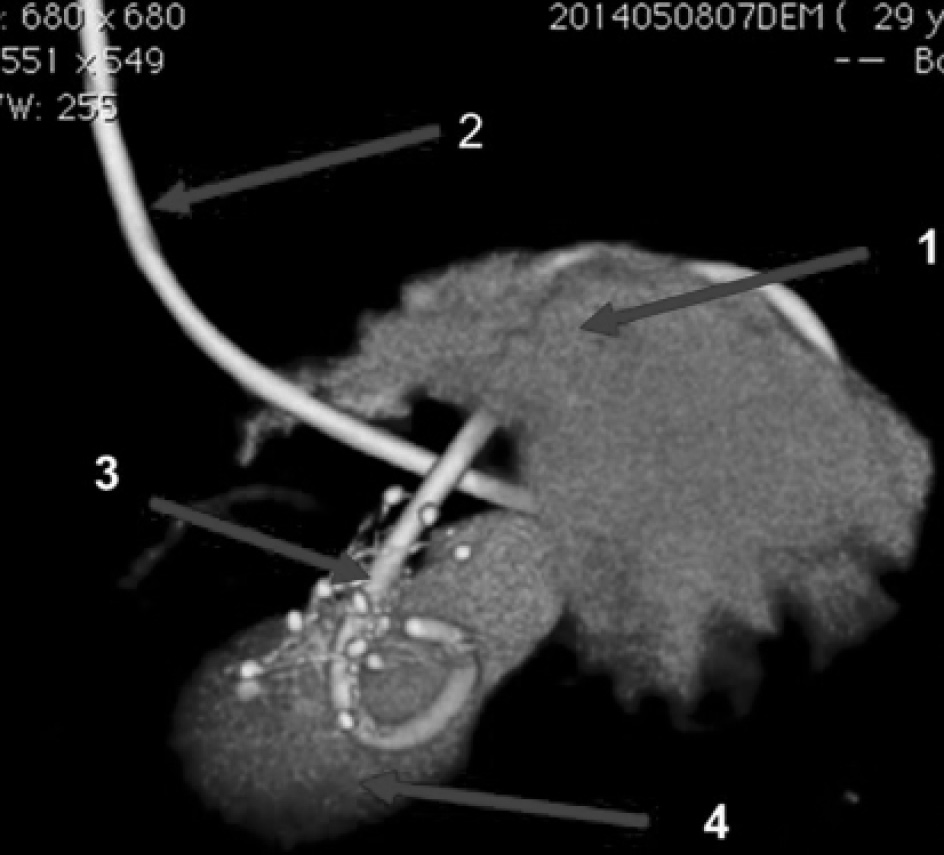

В 7 случаях пациентам с постнекротическими кистами, содержащими секвестры, выполнено эндоскопическое цистогастральное стентирование с использованием металлического покрытого саморасширяющегося стента диаметром 10 мм (рис. 2, 3), с временной установкой санационного цистоназального катетера через просвет стента.

Рис. 3. КТ-3D реконструкция. 1 — просвет желудка; 2 — цистоназальный дренаж; 3 — саморасширяющийся стент; 4 — полость кисты поджелудочной железы